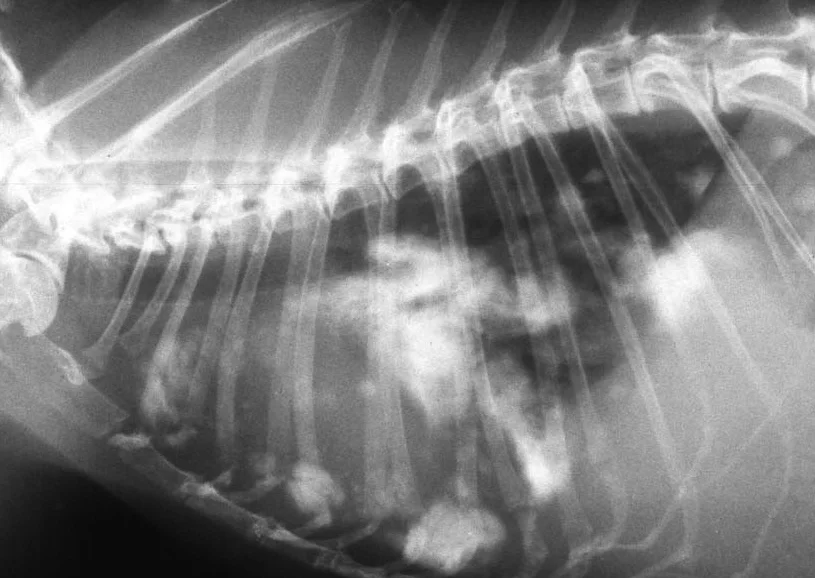

It’s easy to understand why pet owners regularly spay pet dogs and cats. But why spay the pet rabbit, especially if she is a single pet? The reason is preventative health care: the incidence of uterine cancer in unspayed female rabbits is up to 75% in certain breeds. Uterine cancer is usually silent until well advanced. This cancer typically spreads to other body organs, especially to the chest cavity. Signs can include uterine bleeding, lethargy, and difficulty breathing. Early spaying is the key to prevention, and costs much less than trying to treat the sick rabbit later. Prevention is simple: spay your pet rabbit as early as 8-10 weeks of life. Older pets benefit from spaying as well. Our clients also find the spayed female rabbit is calmer, uses the litter box better, and is in general a much better pet. So why spay the pet female guinea pig? Most guinea pigs eventually develop ovarian cysts. These cysts are often benign and cause no apparent harm or distress. However, in a certain percentage of pets, cysts become very large and cause discomfort. Guinea pigs with large painful cysts are often less active, eat less, and lose weight. Pet guinea pigs can be spayed (removal of the entire uterus and ovaries), or in younger animals can have ovariectomy (removal of the ovaries alone), which is a simpler, quicker procedure with an improved recovery time. Questions about spaying your pet rabbit or guinea pig? We would be happy to help. Call the clinic at 317-879-8633.